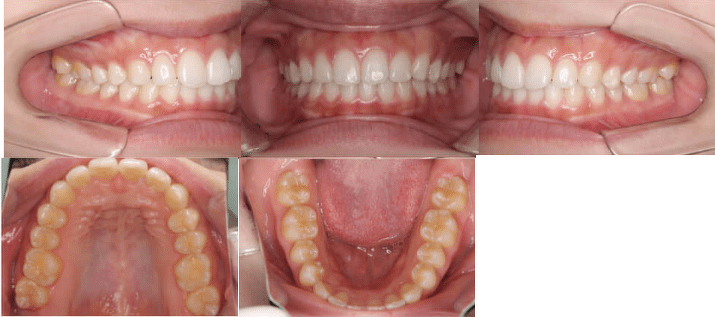

Before

After

| 年齢 | 治療期間 | 費用 | 主訴 | 治療方法 |

| 23歳 | 6ヶ月 | 40万円 | 出っ歯・前歯のすきっ歯を治したい | 非抜歯+マウスピース型矯正装置(インビザライン・薬機法対象外)部分矯正 |

成人の患者さんの症例もご紹介しましょう。

この患者さんは、前歯が前方に捻じれて生えた状態で、前歯の間には隙間ができていました。上の前歯以外にも、下の歯に小さな隙間ができています。症状は「叢生(そうせい)を伴う骨格性I級症例」との診断結果になりました。

この症例では、マウスピース型矯正装置(インビザライン・薬機法対象外)で非抜歯の歯並びの矯正治療を行っています。6ヵ月の治療期間で前歯の開きと捻じれを治療し、隙間なく正しい向きのきれいな歯並びに改善できました。